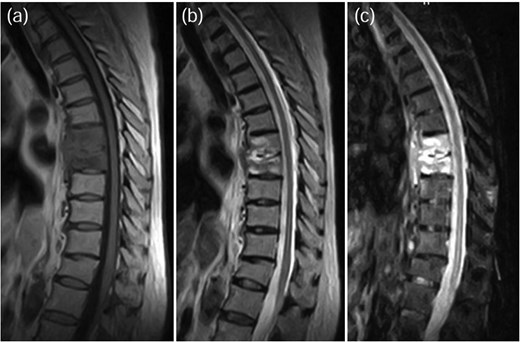

A 78-year-old woman was treated conservatively for an osteoporotic vertebral fracture at L1 with a rigid brace and osteoporosis medication. After 5 months of conservative treatment, her back pain persisted, and she subsequently developed lower limbs symptoms. She experienced severe thigh pain while standing. Plain radiographs showed an intervertebral cleft at L1 (Fig. 4), and a CT scan revealed osteolysis of the L1 vertebral body and the inferior endplate of Th12 (Fig. 5). MRI demonstrated high signal intensity changes in the L1 vertebral body and the anterior paravertebral area at L1-Th12 (Fig. 6). Blood tests showed a normal inflammatory response CRP: 0.28 mg/dL and WBC: 3.7 × 103/μL). A biopsy of the L1 vertebral body revealed the presence of MSSA. The T-scores at the lumbar spine and total hip were −1.4 and −2.3, respectively. The HU value at L1 was 100. Posterior PPS fixation was performed using CAPS at Th11 and L2, along with the placement of a TMC at L1 via a posterior approach (Fig. 7). Eighteen months after surgery, there was no evidence of recurrent infection or screw loosening. The local kyphosis angle was 16° immediately postoperatively and was maintained at 15° at the final follow-up.

MRI demonstrated fluid signals in the L1 vertebral body and the anterior paravertebral area at Th12-L1. These were low-intensity on T1-weighted images (a) and high-intensity on T2-weighted images (b) and not suppressed on STIR images (c).